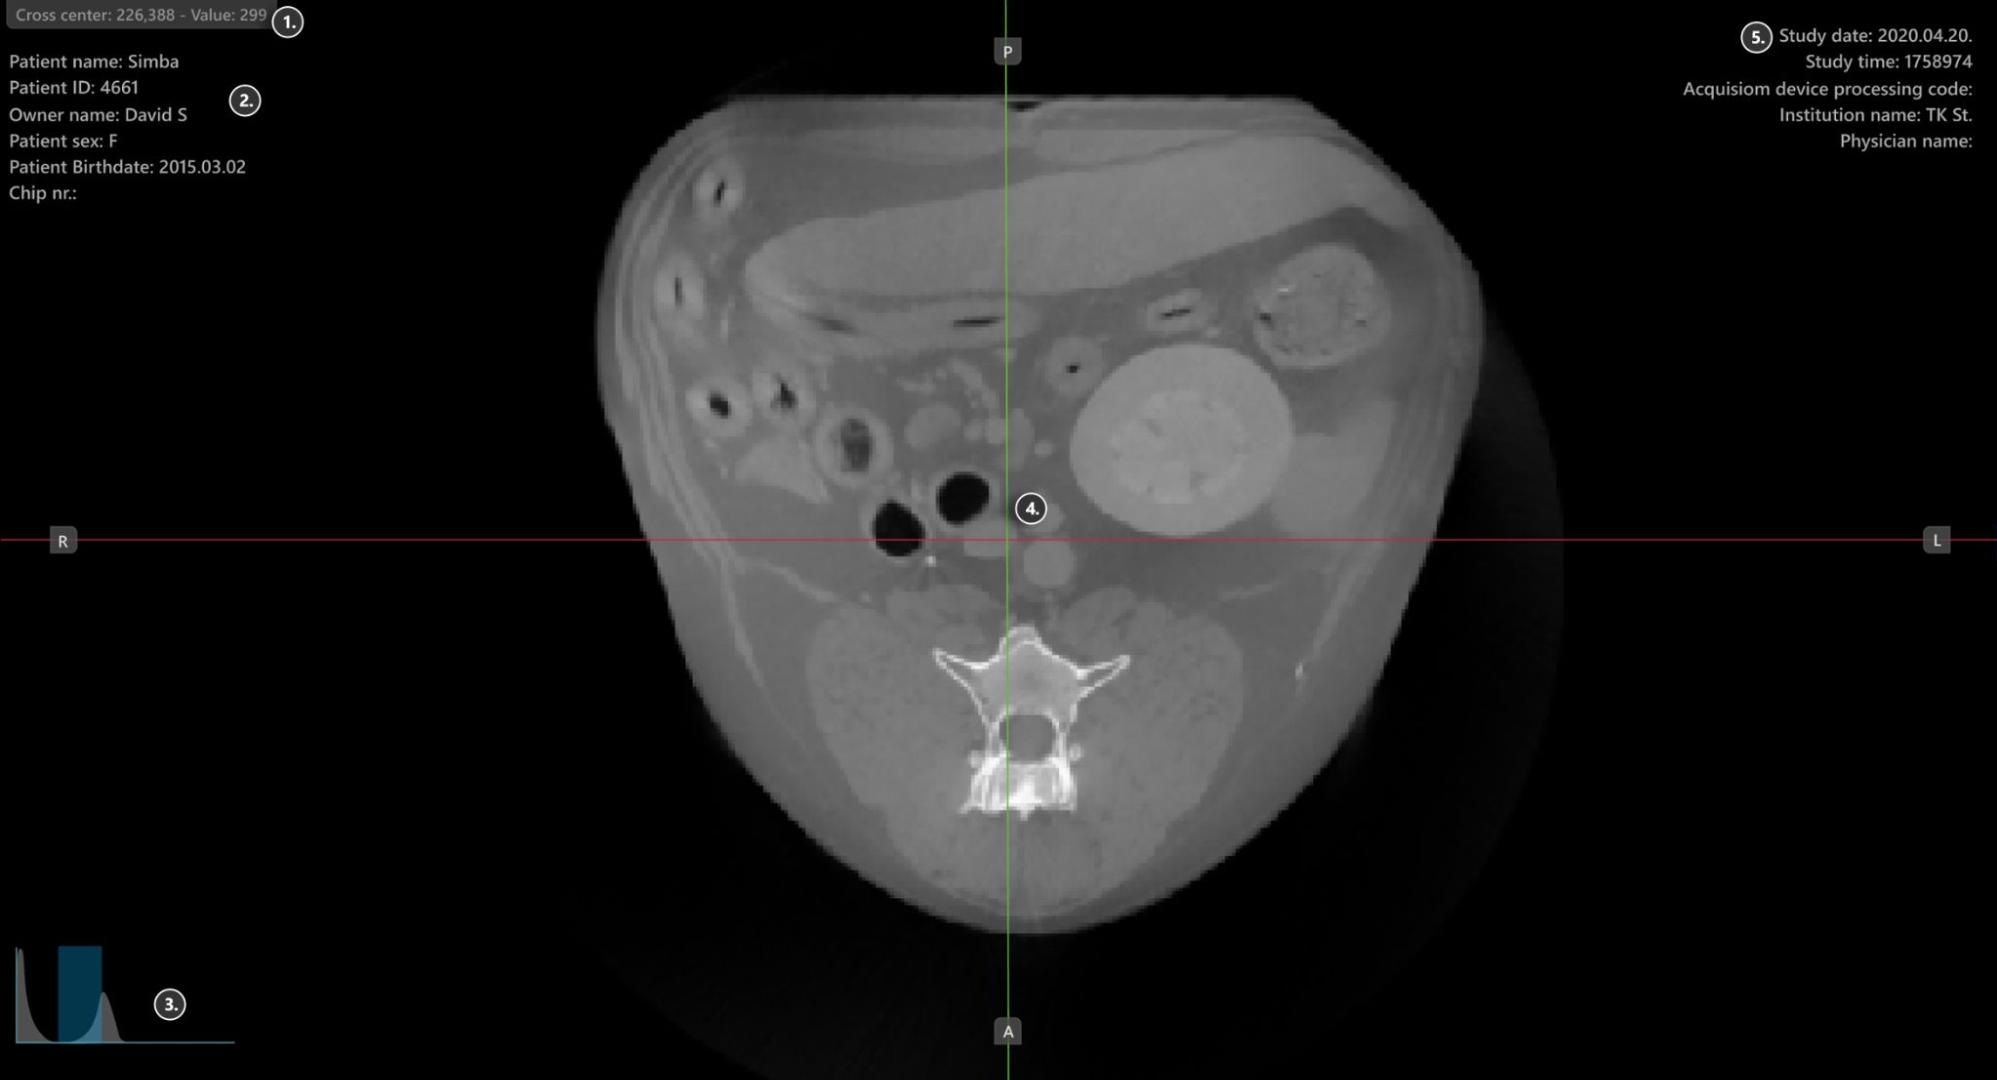

Viewer Area¶

HU (Hounsfield Unit) pixel value

Patient information

Windowing histogram tool

Slicers

Study information